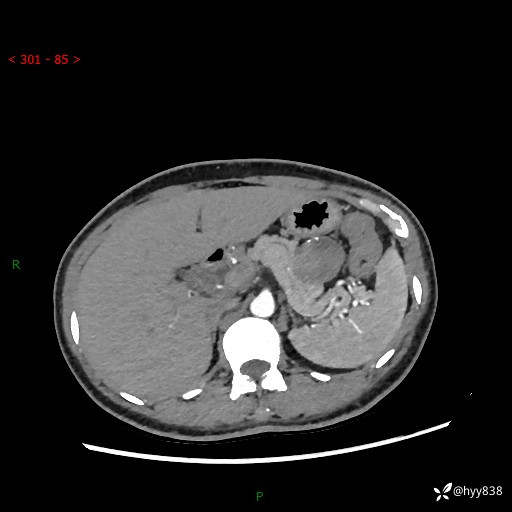

增强动脉期+静脉期

img